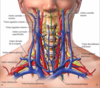

vascularisation du membre supérieur, thorax et abdomen Flashcards